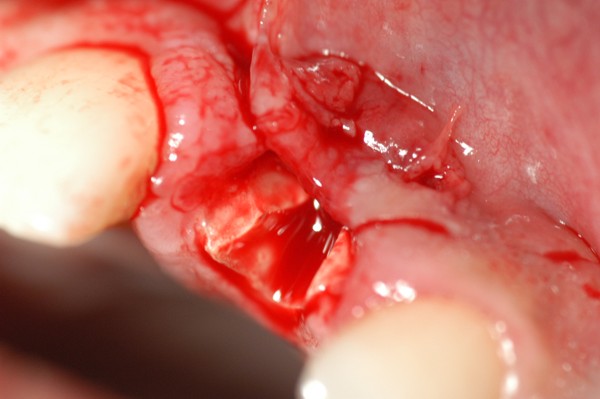

Este artículo pertenece a la categoría: Casos Clínicos

Abstract: Las fuerzas anterógradas traumáticas son en general las causantes de fracturas radiculares en el sector anterior de la boca. Desarrollo: El paciente se presenta a la consulta , con la fractura de una funda de porcelana inyectada en la zona cérvico palatina, solicitando simplemente la reparación en boca para evitar rozamientos linguales. Dicha funda con un perno colado en oro y su correspondiente endodoncia, habían sido realizadas en mi clínica varios años atrás, con un «aparente éxito total». Radiograficamente, se encuentra una fractura radicular cercana al tercio gingival Observada la oclusión de las piezas anteriores, podemos ver que el vínculo ideal de Acoplamiento, no se cumple, habiendo una relación de franco contacto la que ha provocado la fractura. Llevando al paciente a Oclusión en Relación Céntrica, podemos ver el espacio a nivel anterior, correspondiente a la centricidad mandibular. En esa misma posición , es dable percibir una faceta parafuncional mesial del primer premolar superior… …que antagoniza con una faceta parafuncional distal del canino inferior… ..constituyendo un plano inclinado que provoca la antelación mandibular o Discrepancia Horizontal, fracturando la raiz del incisivo central. Extraida la porción coronal de la raiz, pensamos en la realización de un Implante Inmediato, a pesar de la presencia de una fístula dado que se trataba de un central, decisión que obtuvo éxito implantario mas no estético, según veremos luego. Era fundamental conservar lo mas posible las tablas óseas, que de hecho había perdido la porción cervical Realizamos una incisión que conservara las papilas de las piezas adyacentes. Realizamos la exodoncia mediante un instrumento construido «ad hoc» que denomino: Con lo que obtenemos la preservación «ad integrum» de las corticales peridentarias remanentes. Instalamos entonces un implante T.B.R. de 15 mm de largo por 4 mm de diam. con cuello de zirconio de 3,5 mm …quedando tres espiras sin hueso por vestibular, producto de la tabla perdida, Incidimos el periostio a nivel apical del colgajo para obtener mayor paño quirúrgico, y legramos un bolsillo palatino sin incisiones de descarga, para la inserción de la membrana. Suplementamos la carencia ósea vestibular con «BIOSS» …e instalamos una membrana reabsorbible «BIOGUIDE» , que fijamos con el mismo implante, y calzamos por palatino. Suturamos Instalamos nuestra provisional previamente confeccionada, sobre un abuttment de titanio. Y controlamos radiograficamente Pasadas tres semanas del retiro de los puntos, observamos una cicatrización alta que nos muestra el anillo de zirconio del implante. ……………………………………………….. Transcurridos tres meses preparamos una nueva cirugía, dirigida a instalar un injerto autólogo de conectivo en el área del anillo, con un nuevo desplazamiento del colgajo vestibular. Tomamos tejido conectivo del paladar a nivel de los premolares, mediante una incisión mucosa «en libro», y disección del conectivo subyacente. Lo posicionamos en vestibular del anillo de zirconio y lo fijamos mediante sutura Y semanas después nos encontramos con un nuevo fracaso de orden estético. ……………………………………………….. En la actualidad, el caso esta estable , aún con su funda provisional, a la espera de un nuevo intento plástico, mediante Injerto Libre de Encia. ………………………………………………….. ESQUEMA MECÁNICO DEL FENÓMENO …que además de los hechos mostrados en el caso presentado, frecuentemente provocan en el sentido antero posterior los fenómenos de DISPERSIÓN ,en el maxilar superior…y de APIÑAMIENTO en el maxilar inferior. CONCLUSIONES: Además del rigor académico que nos convoca… esta; nuestra casa…nos otorga la confianza que solo da el saber que estamos siempre entre amigos, que cada vez son más. Por tanto es que debo decir: YO fui el responsable de dicha fractura… …porque… …..que hubiera sucedido si hubiera hecho todo el trabajo implantario sin ajustar previamente su oclusión? Seguramente a esta altura del caso…también hubiera fracasado el implante. Siempre decimos que se aprende de los errores más que de los aciertos, y Dr. Carlos A. Acuña Priano

Fig 09(Pie de foto: Exodoncia porción coronal)

Fig.10(Pie de foto: remanente cortical)

Fig.11 Fig.12(Pie de foto: Incisión)